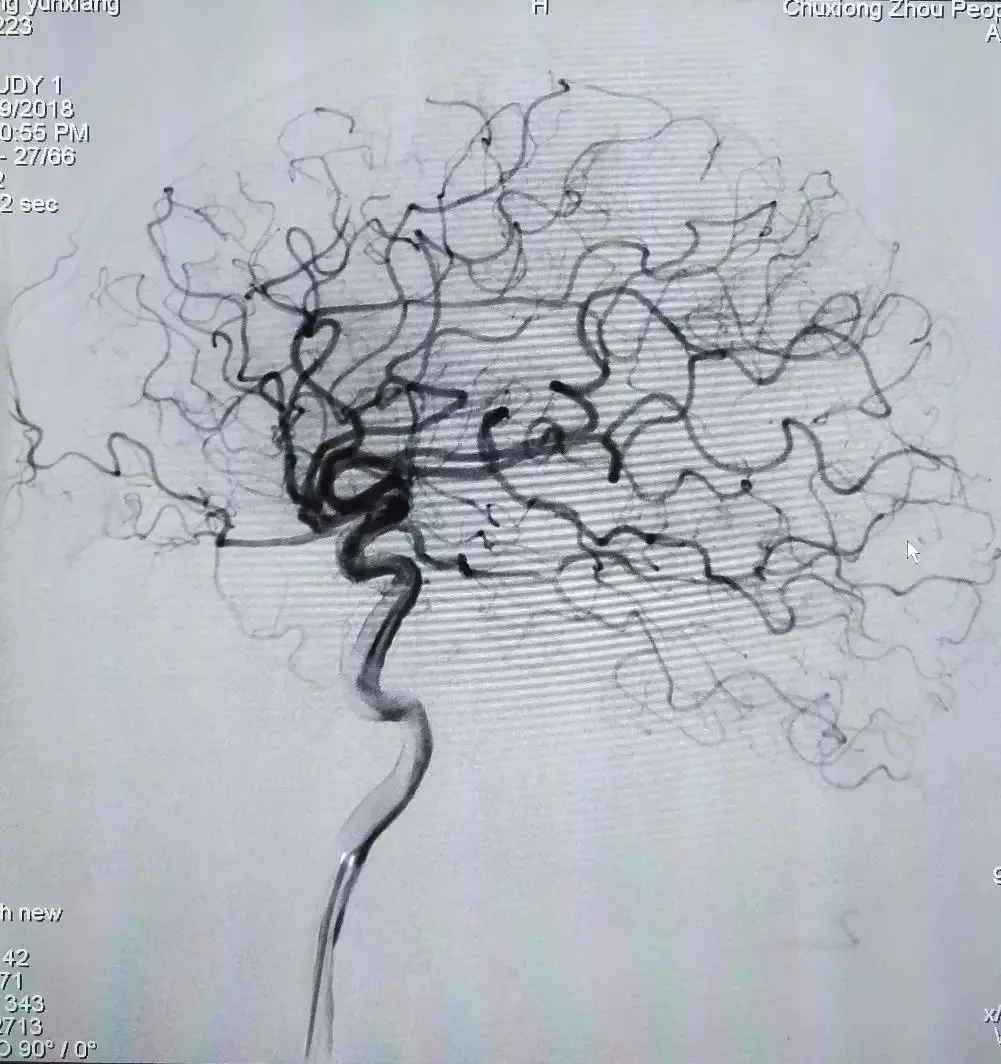

术后造影

观察15min后最终结果

1、发现为原位性狭窄后应及时调整手术策略,避免造成额外的机械并发症。

2、Neuro Rx颅内专用快速交换球囊具备良好的手术即时操作性,与导引导管、导丝等配合良好,在极度迂曲的虹吸弯处能快速通过到达病变,通过性和顺应性好。同时具备良好的回报性,在预处理病变后用于支架后扩张,反复利用,为病人节省费用。